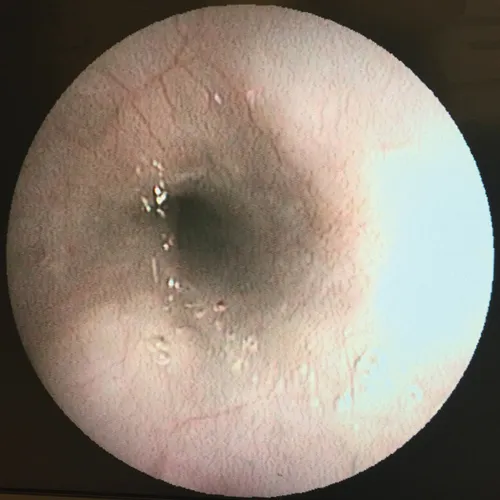

Nearly 20 years after Bryn Tennant's first edition, this new update covers all aspects of diseases and disorders and affecting organs of the abdominal cavity and the endocrine/metabolic system in a case-based format. Responding to advances in imaging technology, digital radiography and high-resolution ultrasonography as well as the growth in specialised diagnostic tests for many diseases, new editor Craig Ruaux brings together a wide variety of new cases.

These cases cover a wide spectrum of metabolic, endocrine, immune-mediated, inflammatory and infectious diseases and range in difficulty from simple bacterial infections to complex, multisystem disorders that would challenge most practitioners. They are presented in random order, as they would appear in everyday practice, and each author brings their own specialist expertise and experience to problem identification and management.

Includes over 150 new, color illustrated cases